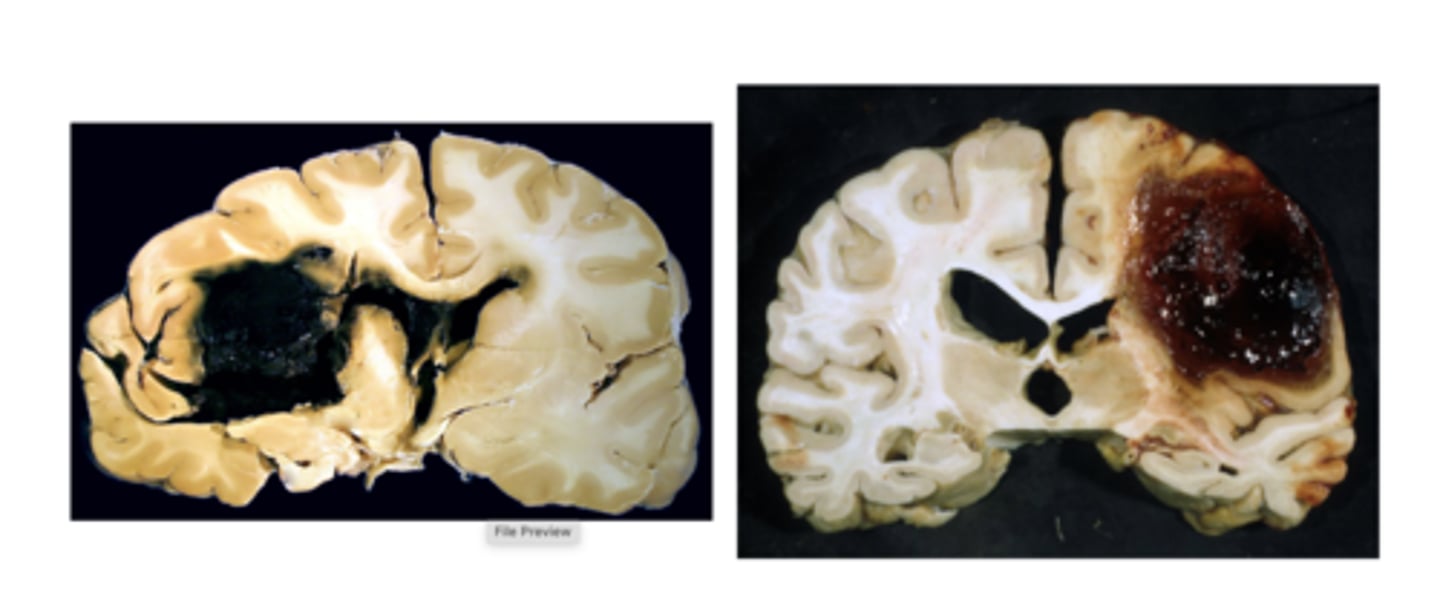

hemorrhagic stroke

intracerebral hemorrhage

Subarachnoid hemorrage

hemorrhagic stroke CT scan

there will be a light spot where the bleeding is

hemorrhagic strokes are named after their

depth and location

intracranical hemorrhage (ICH)

bleeding from an arterial source into the brain parenchyma

- most fatal of all CVA

subarachnoid hemorrage (SAH)

bleeding into the subarachnoid space between the arachnoid and the pia mater